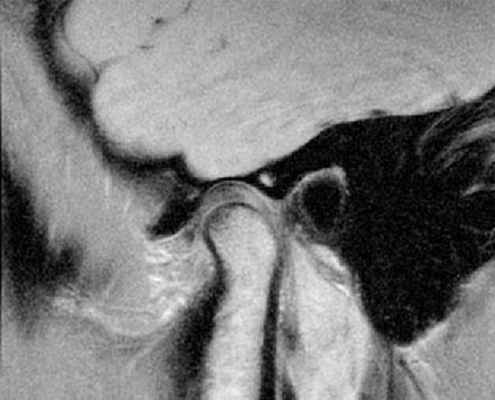

«Застрявший» диск.

«Застрявший» диск. PD sag изображения с открытым (А) и закрытым (Б) ртом - задний край диска (стрелка) остается в нижнечелюстной ямке височной кости. По этой причине открывание рта сильно ограничено. Вероятная причина – образование спаек.